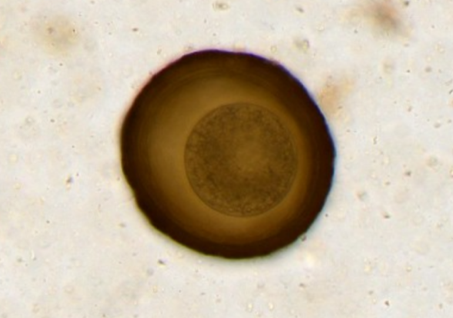

Kit med nødvendig utstyr for påvisning av parasittegg i feces hos hester, med Vetscan Imagyst.

Kit med nødvendig utstyr for prøveforberedelse til fecal flotasjon med fecesprøve fra hest. Til bruk med Zoetis Imagyst helautomatisk digital skanner, for påvisning av parascaris spp. og strongyleegg.